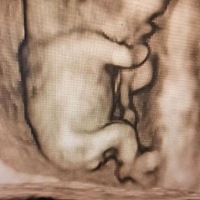

怀孕13周,看不清是不是儿子,有点着急。